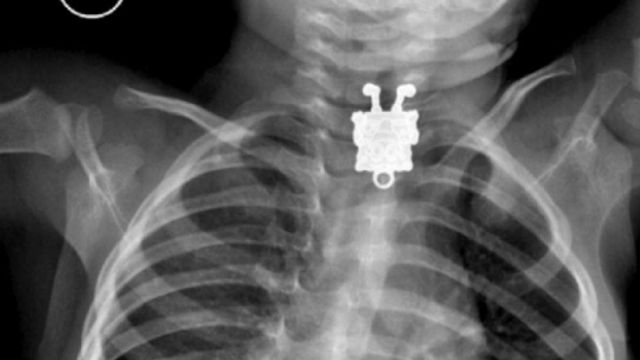

A 16 mesi ingoia il pupazzo di SpongeBob, la radiografia mostra la sagoma del giocattolo

Una sagoma così non poteva passare certo inosservata. Grazie alle radiografie effettuate su un bimbo di soli 16 mesi, è stato possibile capire che il piccolo aveva ingoiato un pupazzo di SpongeBob. E' successo in Arabia Saudita. Il giocattolo è stato rimosso e il bambino, curato presso il King Abdulaziz University Hospital di Jeddah, per fortuna sta bene.